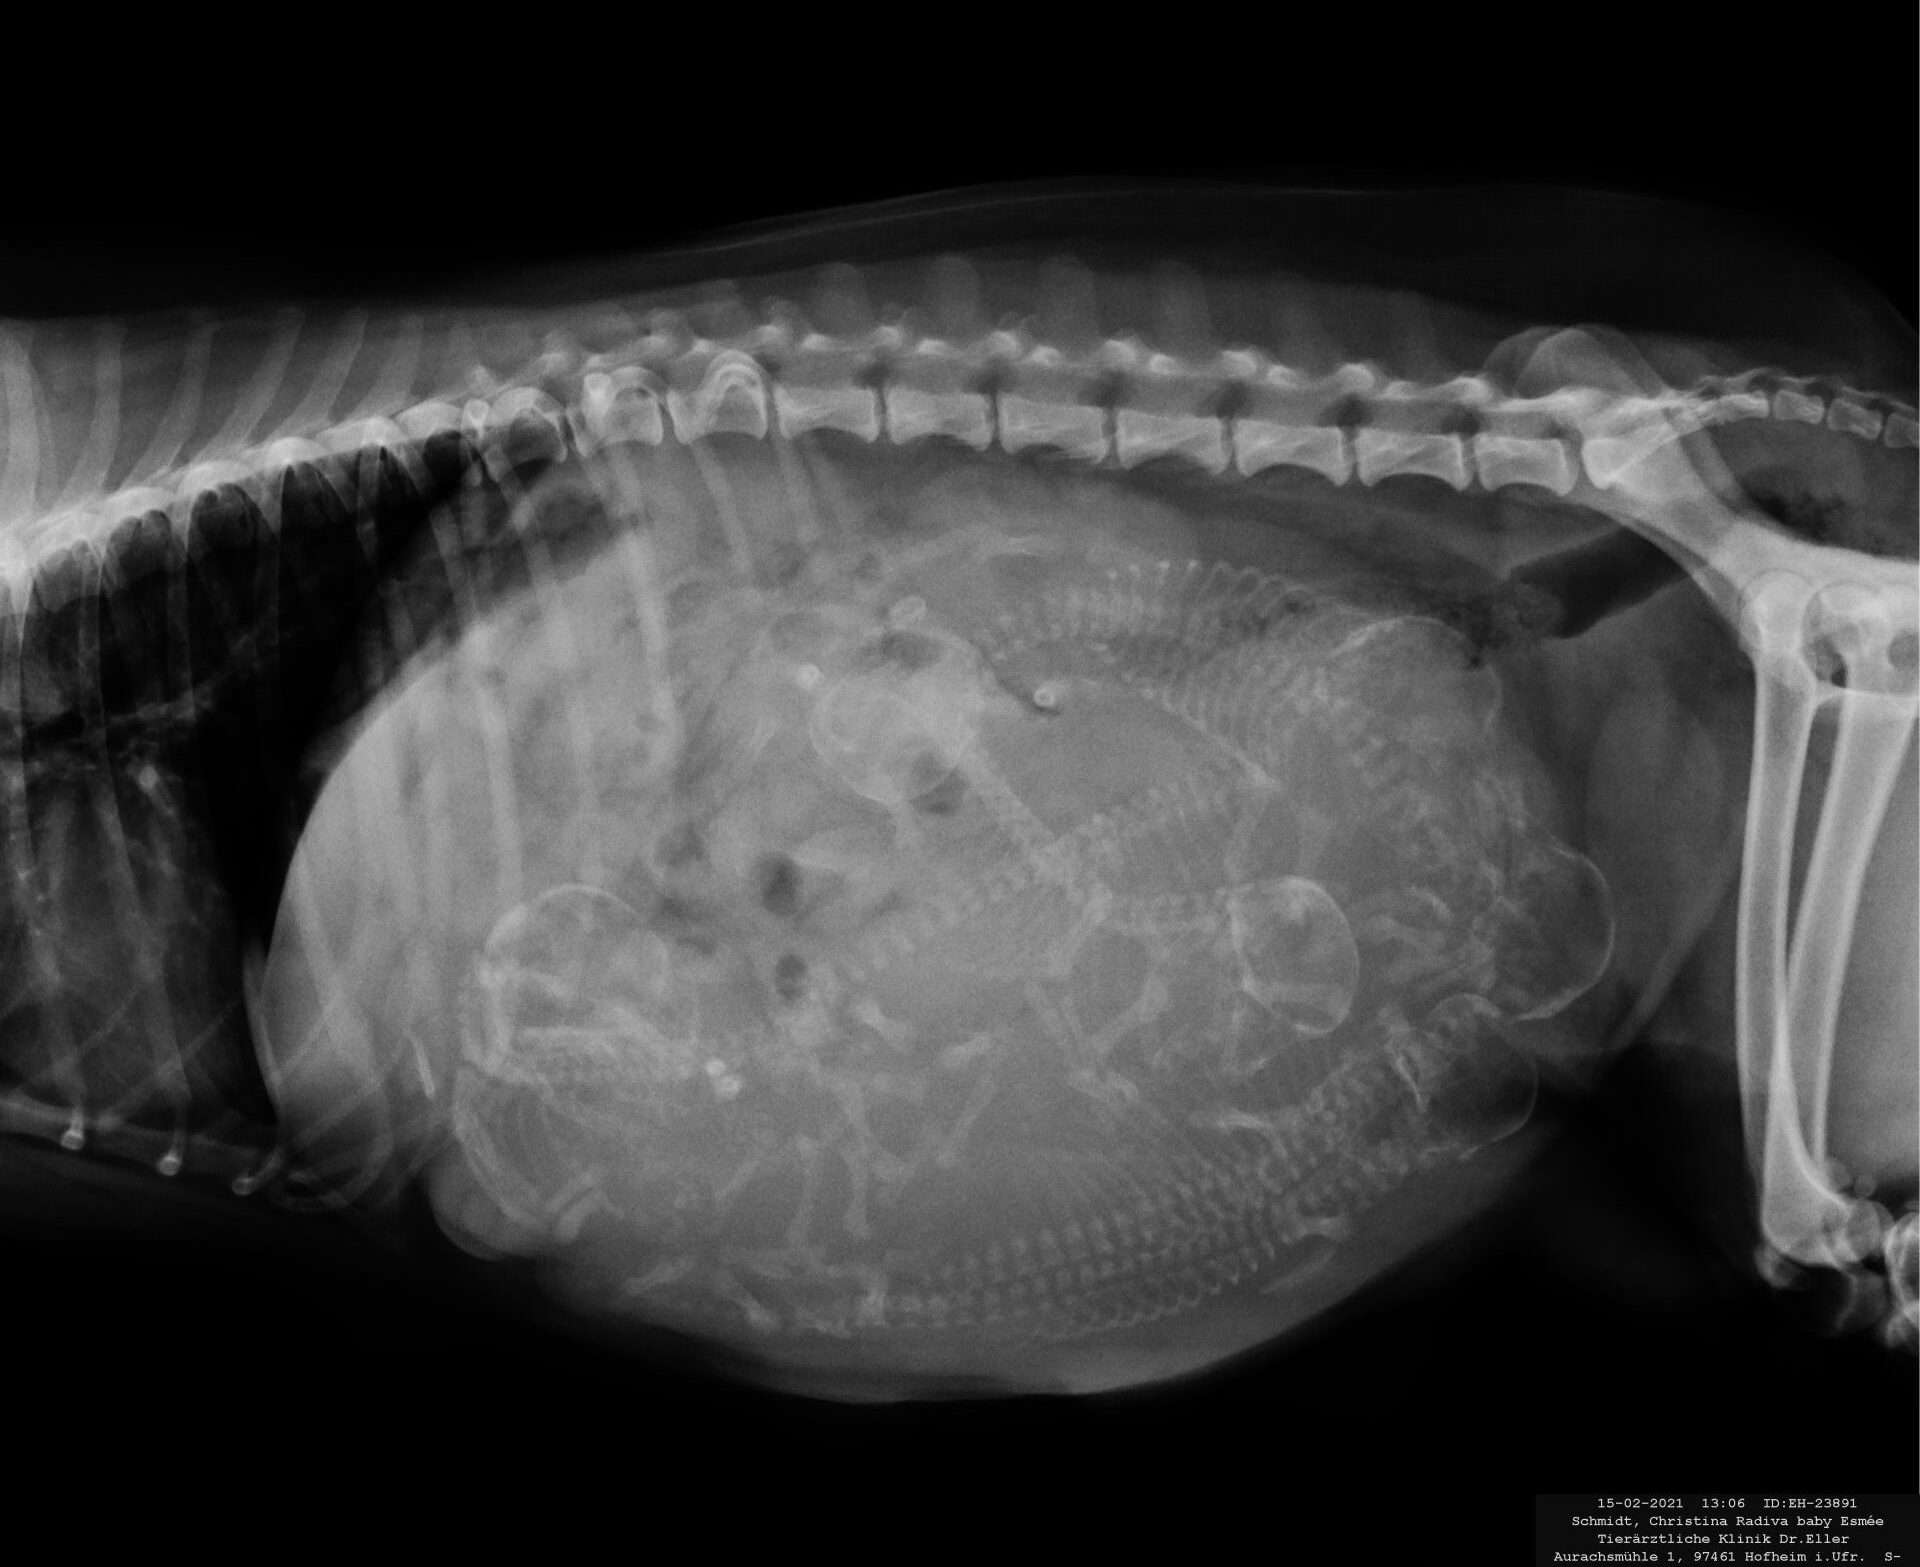

In den bisher knorpeligen Knochen der Föten beginnt die Verkalkung. Die Welpen können nun leicht unter der Bauchdecke ertastet, jedoch schlecht gezählt werden.Die Welpenskelette sind ab dem 42. Tag auf dem Röntgenbild sichtbar. Die Zwerge sind etwa 6,5 cm groß. Jetzt heißt es nur noch "wachsen, wachsen und wachsen"!

Per Röntgenaufnahme lassen sich Anzahl und Größe der Welpen bestimmen.